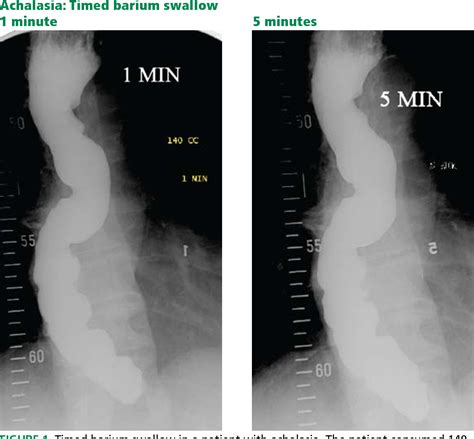

The hallmark finding on a barium swallow study for achalasia is the "bird’s beak" appearance. This occurs because the LES remains tightly closed, causing the esophagus above it to dilate and taper to a narrow point, resembling the beak of a bird. This visual evidence is often the first major indicator that confirms a diagnosis of achalasia.

While the barium swallow is excellent for identifying the structural narrowing and the “bird’s beak” sign, it is often used in conjunction with other tests to confirm the diagnosis and assess the severity of the condition. The following table illustrates how different tests compare in the workup for esophageal motility disorders.

Achalasia Barium Swallow Structural/Functional observation High; identifies "bird's beak" and esophageal dilation.